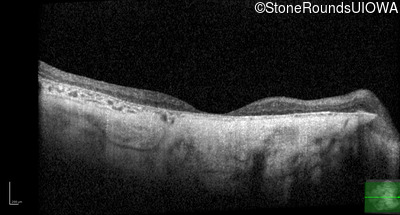

Age at visit: 43 years

OD OS